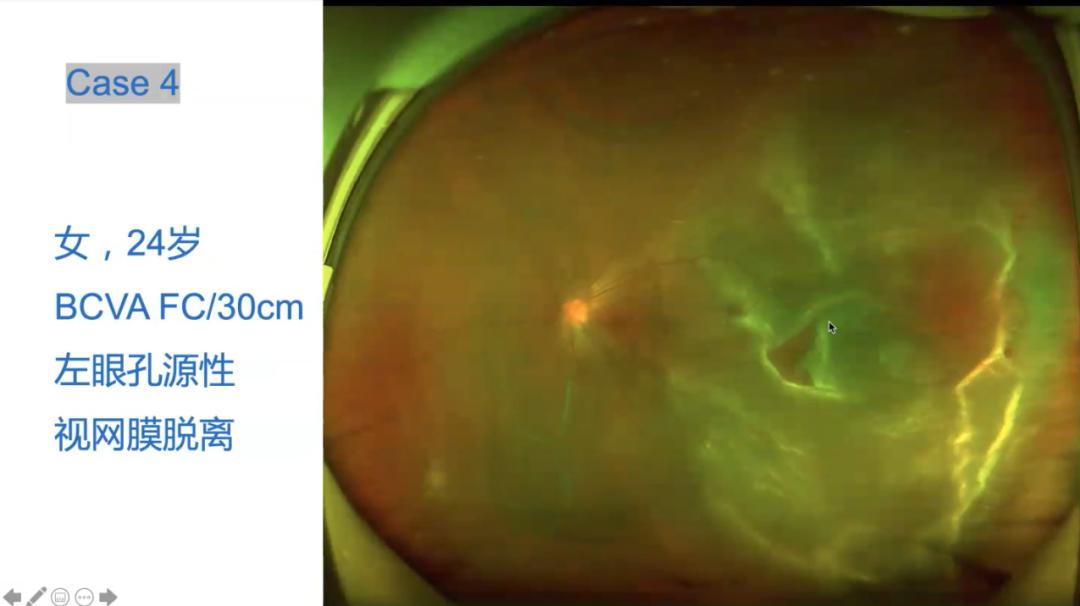

欧堡精品课张静琳院长你不知道你错过了什么视网膜脱离就只是视网膜

图片尺寸1080x606